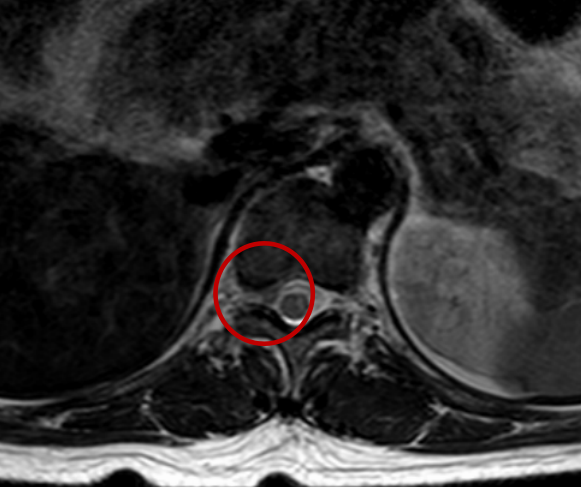

检查结果证明,李女士的胸11/12节段右侧椎间孔处有一块突出的椎间盘组织,恰好压迫到了神经根,这正是导致她一年来反复腰痛的“真凶”——胸椎间盘突出症。

检查结果显示,李女士胸11/12节段右侧椎间孔处发现一突出的椎间盘。